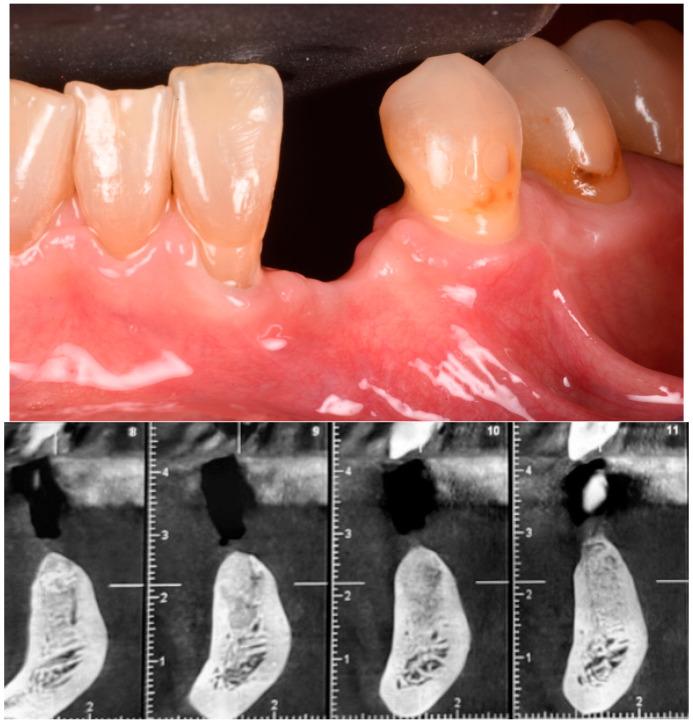

Guided bone regeneration (GBR) has represented a challenge for clinicians in the past 30 years, and the literature has well described many different surgical options such as d-PTFE membranes, titanium grids, or autogenous bone harvested from the posterior mandible. All of the previously mentioned techniques have shown a high rate of complications but, in the last decade, a new membrane made of xenogenic bone was introduced. Most of the publications regarding its application report very few and mild complications. In this article we will suggest a new application using segmented xenogenic bone sheets instead of autogenous bone to correct severe ridge deformity. : Xenogenic bone sheets have been studied extensively over the past decade and have proven effective, with a very low rate of complications when used to reconstruct bone atrophies. The technique presented in this paper aims to reduce morbidity, avoid the need for intra-oral graft harvesting, and minimize both surgical time and post-operative discomfort. : Xenogenic bone sheets of equine origin were used to reconstruct severe 3D bone defects in five patients requiring dental implants. The segmentation of the sheet allowed the operator to rebuild the missing bone walls and achieve optimal anatomy without compromise. Furthermore, using different sizes and thicknesses of the bone sheets allowed safe procedures preventing early exposure of the membranes. CBCT of the defects before and after 8 months of healing were measured with Exocad software to assess the volumetric gain. Histological analysis performed on one site showed integration of the bone lamina and live bone underneath. : In all five cases evaluated the ridge deformities were successfully corrected and all patients' implants have functioned for more than two years to date. The average horizontal bone gain in these five cases was 6.18 mm (±1.19 mm) while the vertical gain was 9.70 mm (±2.39 mm). : This new application of flex cortical sheets simplifies the surgical procedure for both operator and patient, reduces morbidity and post-operative complications, and shows promising signs for resolving complex 3D bone reconstructions.

在过去30年里,引导骨再生(GBR)一直是临床医生面临的一项挑战,文献中已经详细描述了许多不同的手术选择,如双层聚四氟乙烯(d-PTFE)膜、钛网或从下颌后部获取的自体骨。上述所有技术都显示出较高的并发症发生率,但在过去十年中,一种由异种骨制成的新型膜被引入。关于其应用的大多数出版物报告的并发症很少且很轻微。在本文中,我们将提出一种使用分段异种骨片代替自体骨来矫正严重牙槽嵴畸形的新应用。:在过去十年中,异种骨片已被广泛研究,并已被证明是有效的,用于重建骨萎缩时并发症发生率非常低。本文介绍的技术旨在降低发病率,避免口内取骨的需要,并将手术时间和术后不适降至最低。:使用马源异种骨片为五名需要种植牙的患者重建严重的三维骨缺损。骨片的分段使手术者能够重建缺失的骨壁并实现最佳解剖结构而不受影响。此外,使用不同尺寸和厚度的骨片可进行安全操作,防止膜过早暴露。使用Exocad软件测量愈合8个月前后缺损的锥形束计算机断层扫描(CBCT),以评估体积增加情况。对一个部位进行的组织学分析显示骨板与下方活骨的整合。:在评估的所有五例病例中,牙槽嵴畸形均得到成功矫正,所有患者的种植体至今已正常使用两年多。这五例病例的平均水平骨增量为6.18毫米(±1.19毫米),而垂直增量为9.70毫米(±2.39毫米)。:这种柔性皮质骨片的新应用简化了手术者和患者的手术过程,降低了发病率和术后并发症,并显示出解决复杂三维骨重建问题的良好前景。